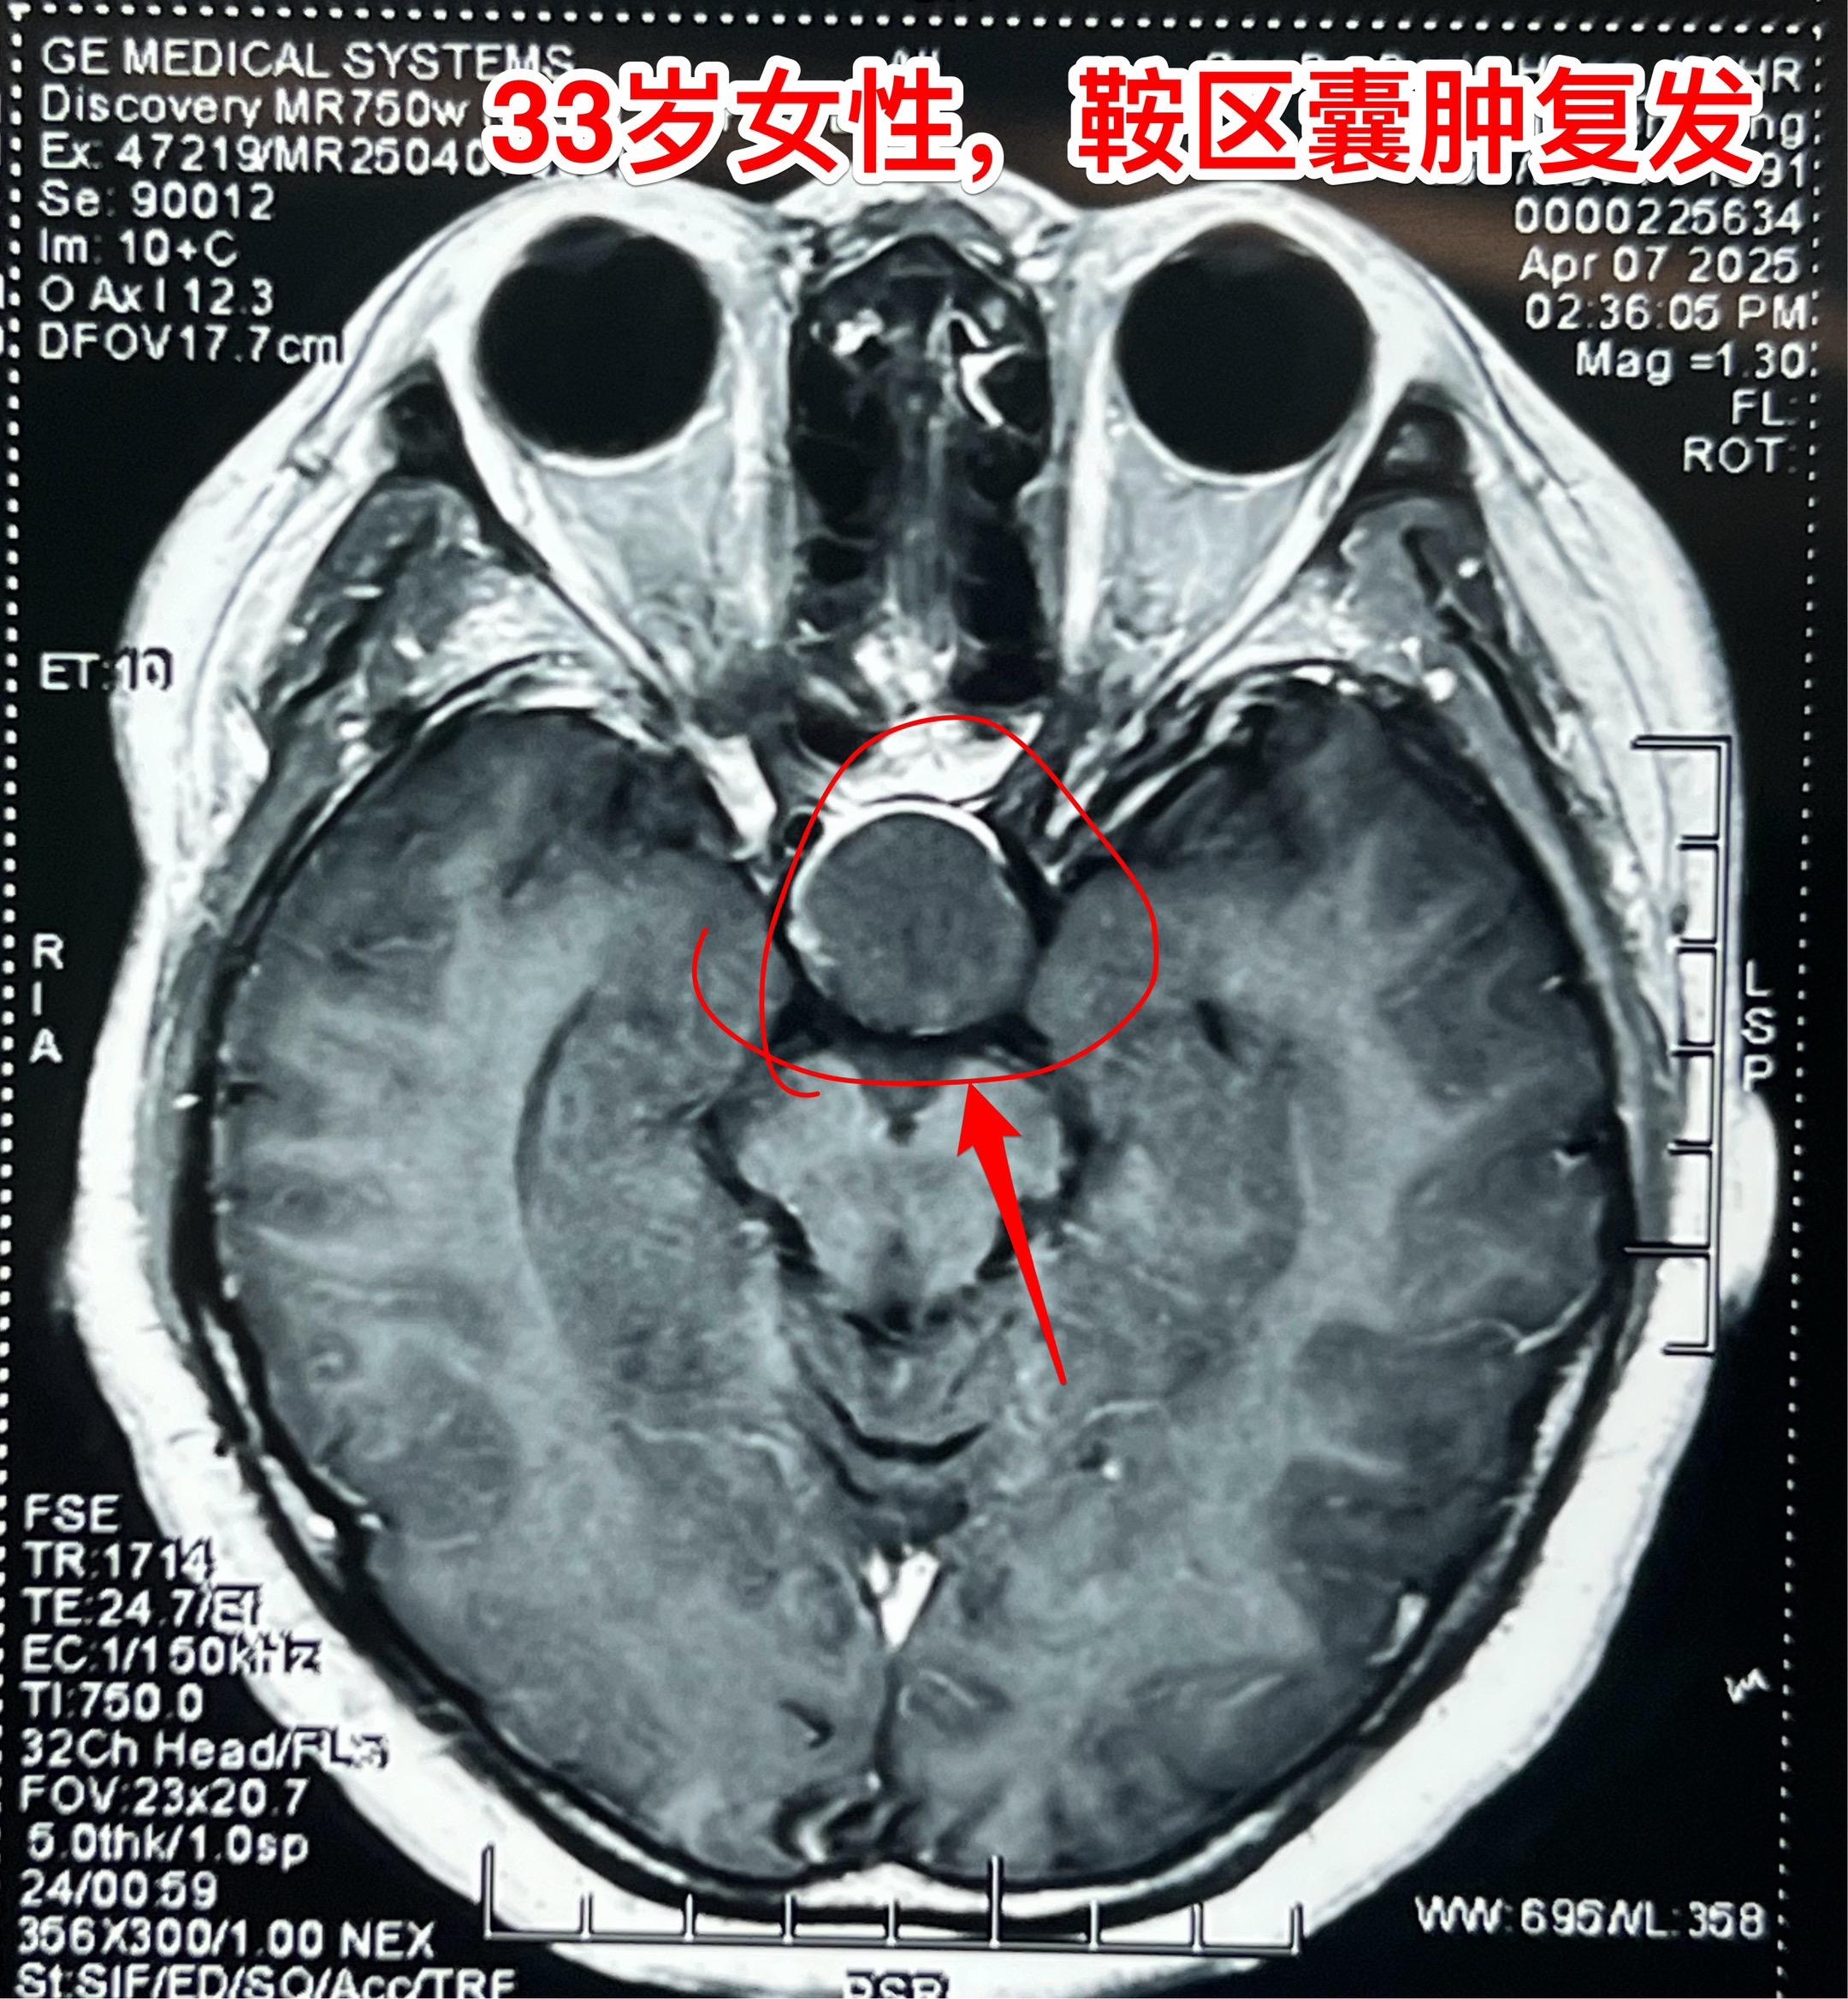

33岁女性鞍区囊肿手术后复发再次手术。这个湖北女性第一次手术是在2025年1月作的经鼻手术,手术后病理报告只看见一些无细胞的结构,没有得出明确的诊断结论(有些遗憾哦)! 手术后两个月患者感觉视野受损,复磁共振显示囊肿和手术之前几乎一样大。 也许是有了心理阴影,这次患者决定找我作开颅手术。开颅手术可以取得确切的病灶标本,最终会得到明确的病理诊断,这是其一大优点! 4月12日作了手术,手术中看见囊肿内涵粘稠液体,可以拉丝,符合拉克氏囊肿。手术中证实:CT上看见的